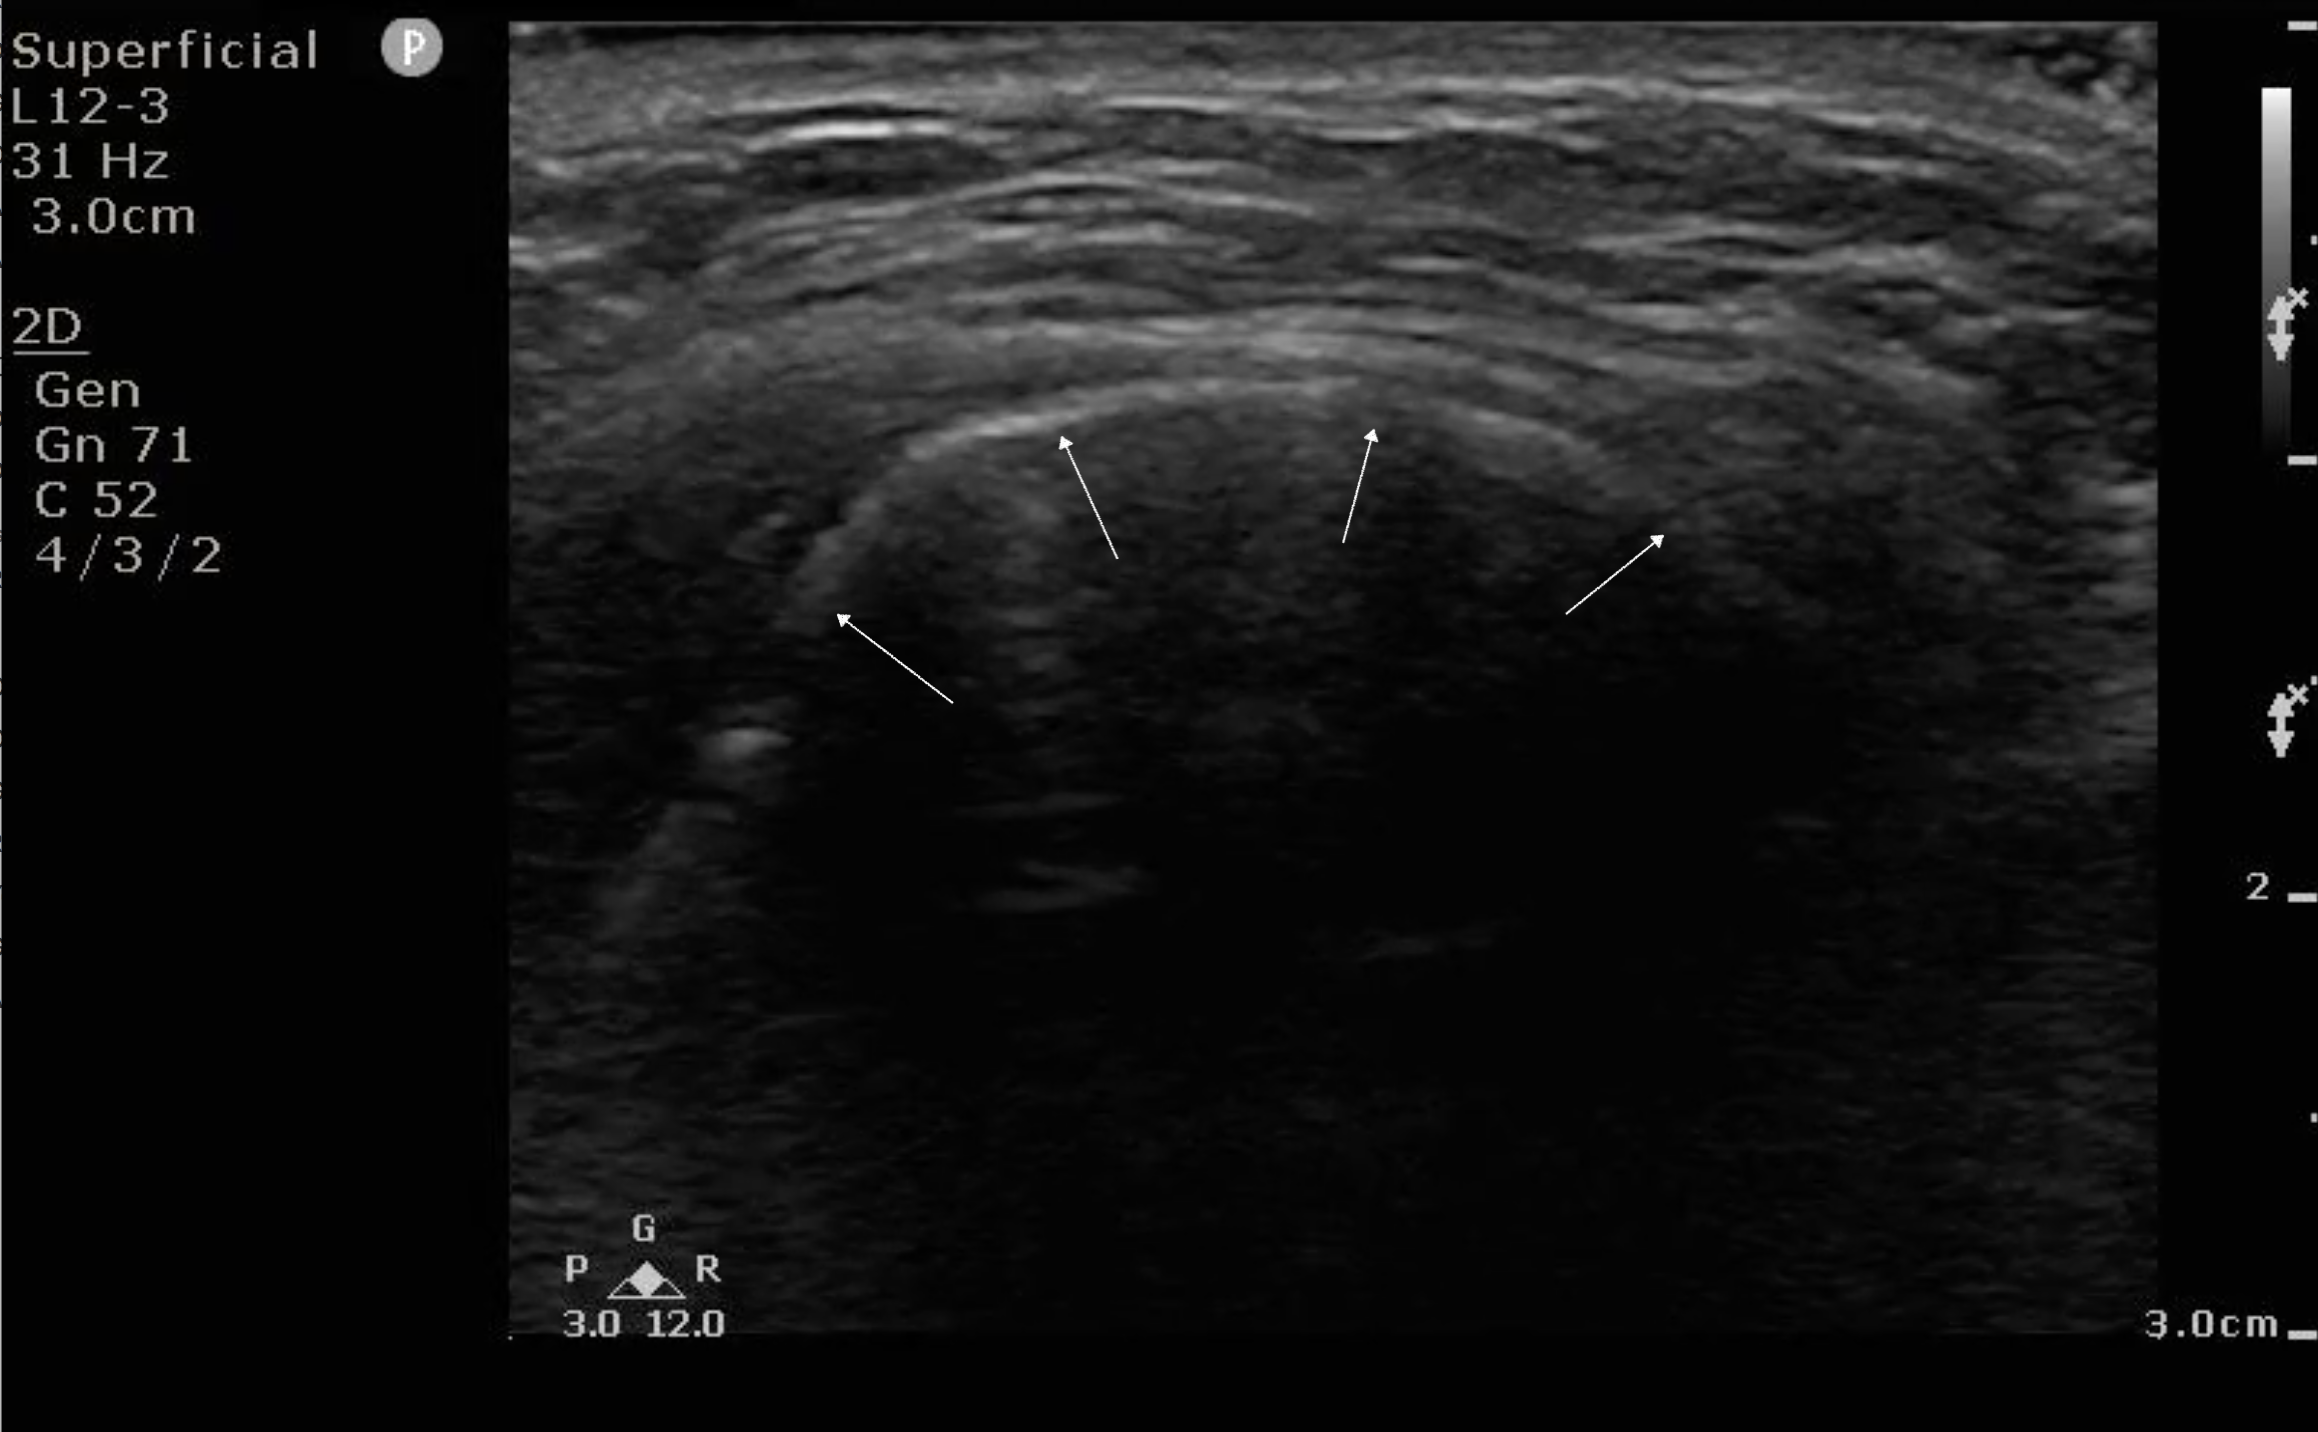

- Figure 3a and b. Step 3: Sliding down the neck ever so slightly and keeping the angle of the probe approximately the same as finding the hyoid bone, you will see a hypoechoic band in the far field with two circular hypoechoic structures in the near field, forming a frog face-like image. The hypoechoic band is the epiglottis (E) and the two circular structures are strap muscles (SM) of the neck. Normal thickness of the epiglottis in adults is <3mm. Far field to the epiglottis are hyperechoic artifacts due to air; the bright linear line is the air-mucosal interface.